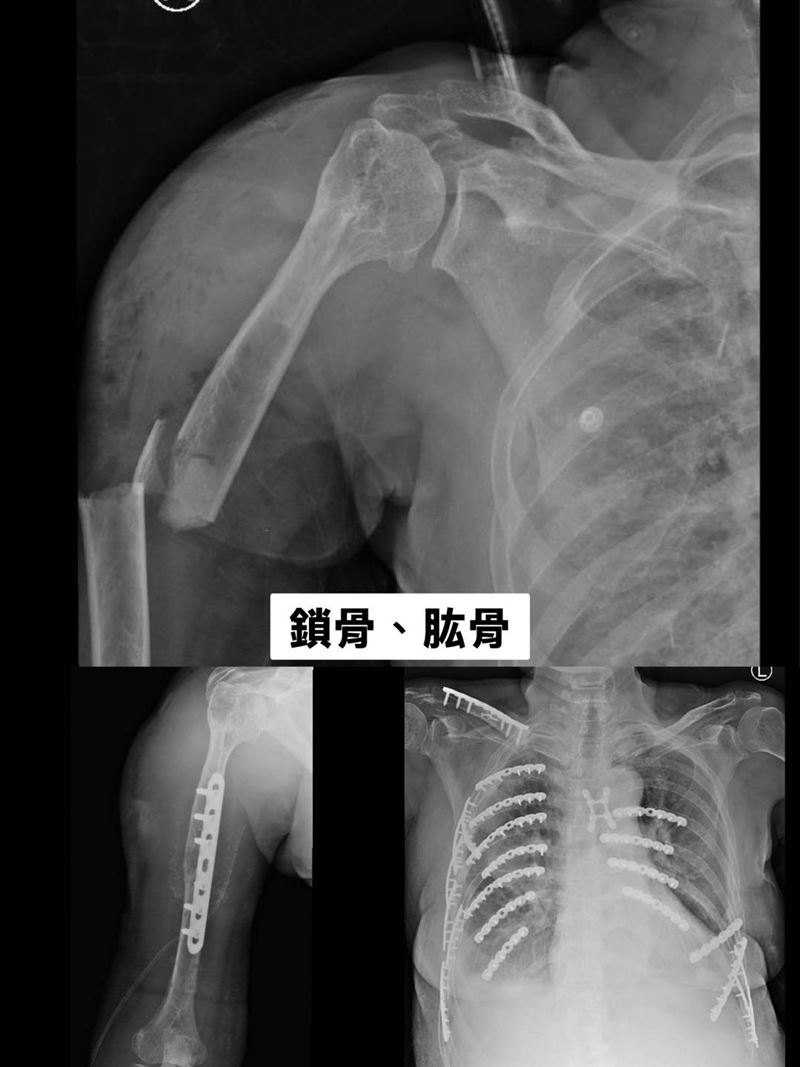

骨科醫師陳柏辰形容,黃婦破碎的骨頭如同散落的拼圖,儘管傷勢嚴重,但她在加護病房仍保持清醒,咬著呼吸管以眼神傳達求生意志,令人動容。(圖/衛福部彰化醫院提供)

林聿騰指出,整個變形的胸腔透過3D胸廓重組影像定位後進行微創手術,以鈦合金骨板及骨釘進行肋骨固定,穩定整個胸腔,讓患者可以正常呼吸,再交由骨科手術。

骨科醫師陳柏辰提到,黃婦破碎的骨頭如同散落的拼圖,團隊們一次次在手術台上,細心地將每一塊骨頭拼回原位並固定。令人動容的是,黃婦一直很堅毅,即使在加護病房仍保持清醒,咬著呼吸管、全身動彈不得,卻依然努力睜開眼睛,用堅定的目光向他致意。「那雙眼睛裡,充滿了鬥志與希望。她沒有一句抱怨,只有想活下去的力量。」